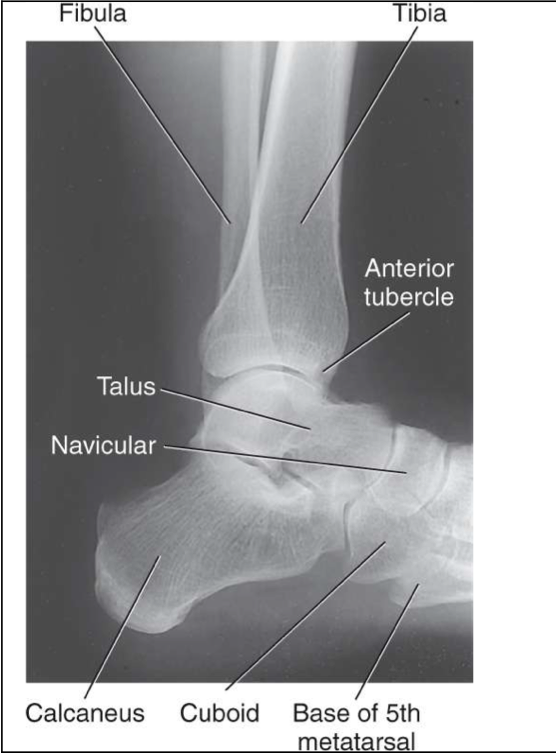

AP Ankle

Patient Position

Sitting or lying on table

o Can be standing

Affected leg extended on table

Part Position

Foot is dorsiflexed to form a right angle to tib/fib

Note: we don’t force this if there is an injury

Intermalleolar line forms a 15-20 degree angle to the IR

CR

Perpendicular to a point midway between malleoli

Collimation

Include approx of 1/3 tib/fib, talus and proximal metatarsals

Must include base of 5th metatarsal

Evaluation Criteria of AP ankle

Distal ⅓ of tibia and fibula demonstrated

Proximal ½ of metatarsals included

Medial and superior aspect of Mortise joint open

Lateral distal tibia+ lateral talus superimposed over fibula

Closed lateral Mortise joint

Lateral Ankle

Lying on affected side with lateral ankle against IR

Foot dorsiflexed to place foot at right angle to tib/fib

Affected ankle in a true lateral

Lateral malleolus located 1 cm posterior to the medial malleolus

perpendicular to medial malleolus

to include entire ankle joint, distal tib/fib and base of 5th metatarsal

especially the base of the 5th

Evaluation Criteria of lateral ankle

Entire talus and calcaneus visualized

Base of 5th metatarsal demonstrated

Lateral malleolus superimposed over posterior half of tibia

Talar domes superimposed & tibiotalar joint is open

Optimal exposure factors – visualize the distal fibula through the talus.

Should see anterior pretalar and posterior pericapsular fat pads

Note: Foot must be dorsiflexed 90° for anterior pretalar fat pad to properly demonstrated